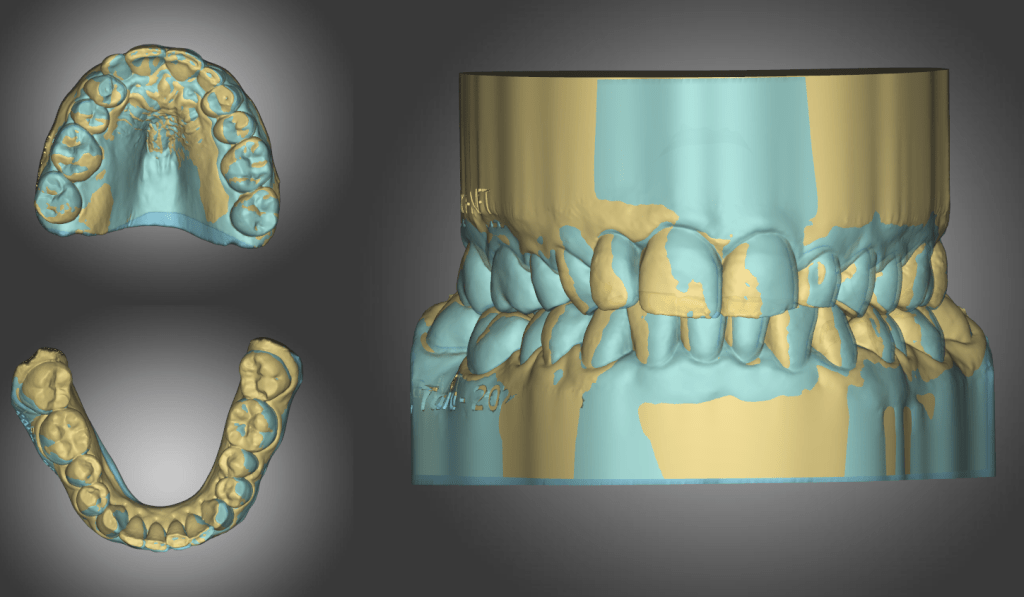

Mackenzie. L – Myobrace – Age 9

Adaptive Orthodontics TREATMENT STARTED AT AGE : 9 Myobrace K1 MediumMixed DentitionClass 2 Div IModerate 1st Review – 2023-03-01 YELLOW = Initial 2022-10-29 BLUE = 1st Review 2023-03-01 Compliance was not good in the first quarter. Not much expansion seen on buccal side 2nd Review – 2023-05-30 YELLOW = Initial 2022-10-29 BLUE = 2nd Review2023-05-30… Read.